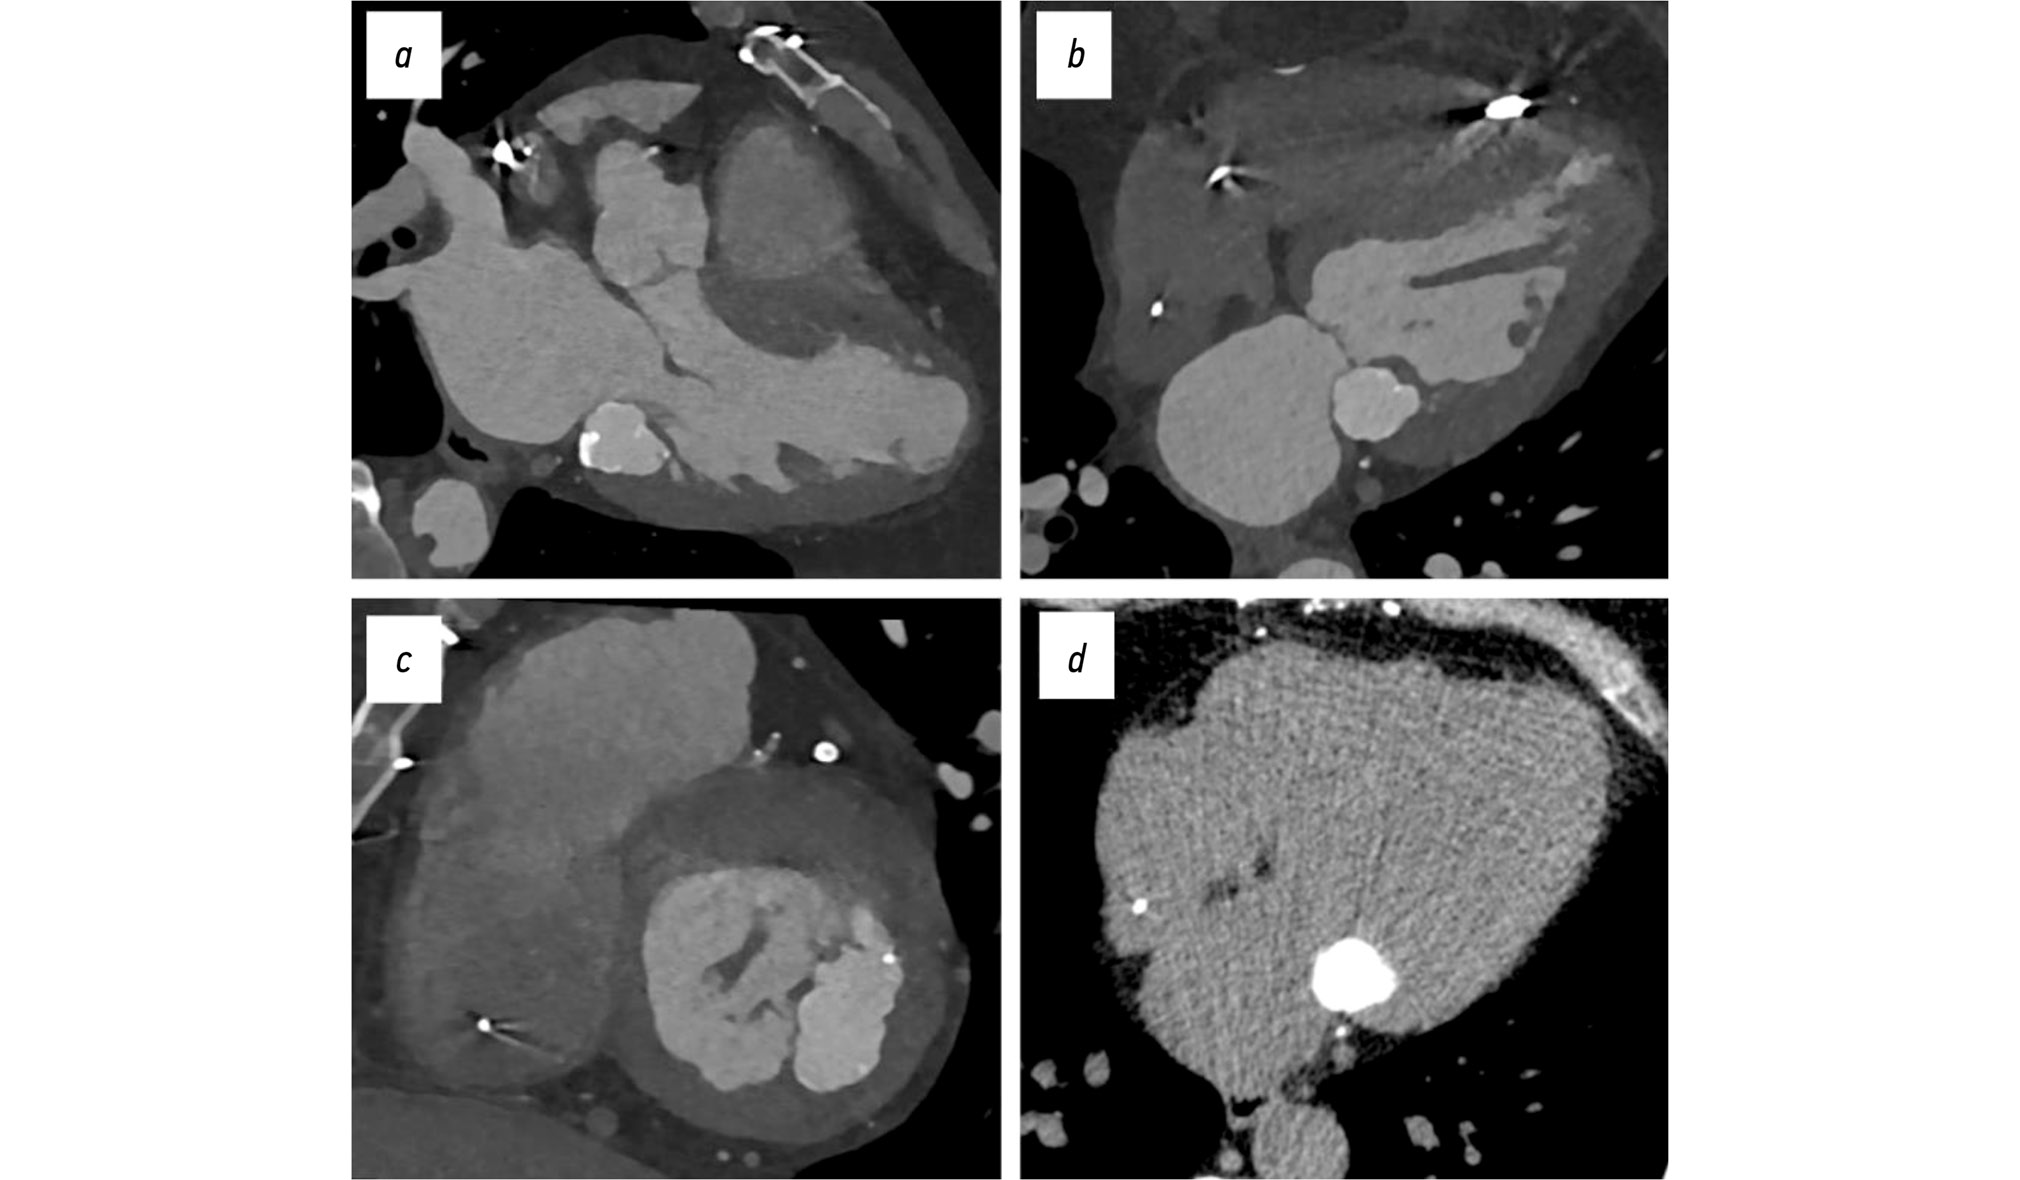

Transthoracic echocardiography revealed a left ventricular apical aneurysm, moderate hypertrophy of the remaining viable myocardium, dilation of all cardiac chambers, and moderately reduced global contractility. Atherosclerotic changes were observed in the aorta, aortic valve, and mitral valve. Additionally, grade II–III mitral and tricuspid regurgitation and grade I pulmonary hypertension were noted. A fixed, hyperechoic mass measuring 28 × 26 × 37 mm was identified near the posterior mitral leaflet. The mass lacked acoustic shadowing and showed no evidence of blood flow. It appeared to be adjacent to or arising from the posterior basal segment of the left ventricle, the posterior mitral leaflet, or the mitral annulus (Fig. 1). Retrospective evaluation of echocardiograms from May 2017 and October 2018 showed a large calcification at the site of the lesion.

Fig. 1. Transthoracic echocardiography, B-mode, clinical case 1: a–c, mass located near the posterior mitral leaflet; d, evidence of mitral regurgitation on Doppler ultrasonography; a, parasternal long-axis view; b, apical four-chamber view; c, parasternal short-axis view at the mitral valve level; d, apical two-chamber view.